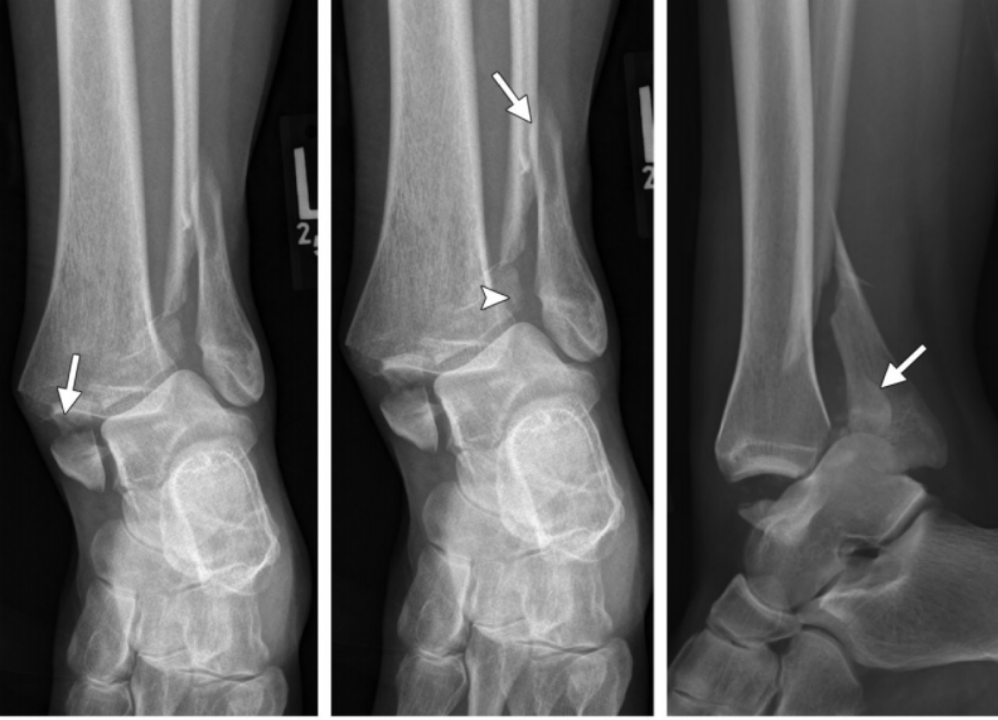

Ⅱ 度:由于距骨给腓骨施加了旋转力,导致腓骨在胫骨关节面顶部发生斜行或螺旋形骨折,骨折线一般自前下方斜向后上方。

II 度损伤 X 线片显示:胫腓骨间隙变宽,提示下胫腓前韧带断裂;腓骨螺旋形骨折;侧位片显示腓骨骨折位于下胫腓联合水平,骨折线由前下到后上,后踝无骨折。

Ⅲ 度:若外旋的力量进一步作用,可导致下胫腓后韧带断裂,或韧带在腓骨后结节附着点撕脱,或其胫骨附着点撕脱骨折(Volkmann 骨折)。

IV 度损伤 X 线片显示:胫骨腓骨间隙变宽,提示下胫腓韧带联合断裂;腓骨螺旋形骨折,腓骨骨折位于下胫腓联合水平,骨折线由前下到后上,内踝间隙增宽,提示三角韧带断裂;侧位片显示后踝无明显骨折,但下胫腓后韧带可能断裂。